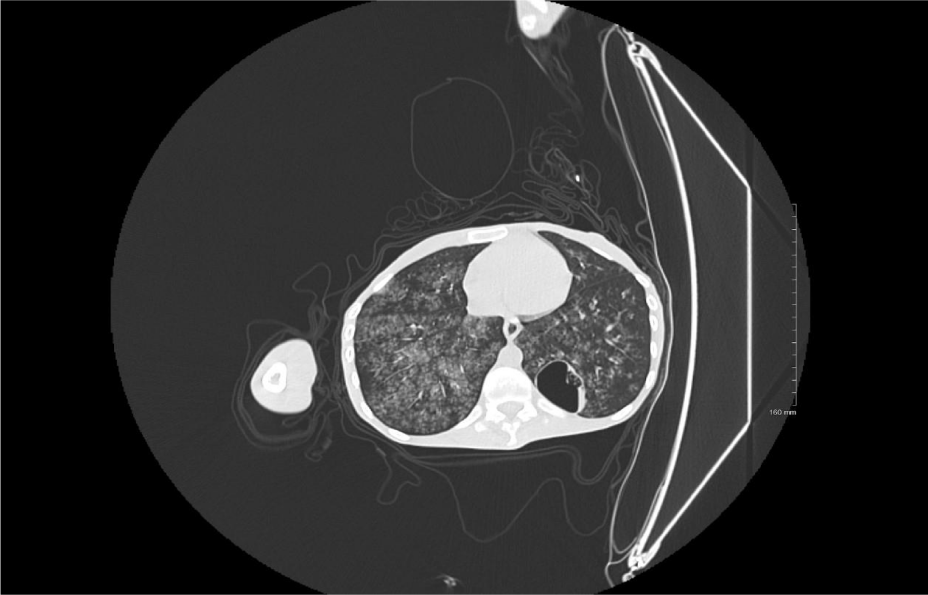

The CT performed in February 2022 (Figure 2) showed opacification of the largest cyst in the right lower lung lobe suggestive of an autoimmune disease. However, the patient’s results were negative for Anti-Neutrophil Cytoplasmic Antibodies (ANCA) and rheumatoid factor. The primary team decided to perform a biopsy of the lesion to establish a definitive diagnosis.

The primary medical team decided to perform a biopsy of the lesion to establish a definitive diagnosis. Another CT was performed later that month when the patient underwent a CT-guided biopsy procedure, which targeted the solid nodule with the use of a 17G coaxial system. Four good cores were successfully acquired (Figure 3).

Shortly after the procedure, the patient developed hemoptysis and became unstable. Another CT scan was conducted soon thereafter which did not reveal pneumothorax. However, bilateral ground glass opacities were observed. Owing to the presence of hemoptysis, the findings were associated with alveolar hemorrhage that was likely secondary to aspiration. The patient had a normal coagulation profile (Figure 4).